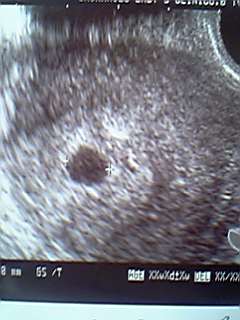

エコーの画面をじっと眺める。

小さな丸が目に飛び込んできた。

これが胎のうっていうあれかな。

先生が、その大きさを測って写真をパチリ。

まだ9ミリだって。

ホントは今日で5w2dのはずだけど、内診台を降りるとそれは訂正され4w6dだって。

ちょっと混乱したけど、胎のうの大きさで決めるのであって、周期には誤差もあるのだとか。

とにかく今は順調だということ。

とりあえずホッとして、そのエコーの写真をいただいたので、大事に持って帰ってきた。

結果を伝え、2人で喜びをかみしめ、エコー写真をじっと見つめる。

まだよく分からなくて実感しづらいけど、そのエコー写真と一緒に記念撮影。